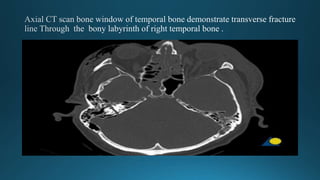

Transverse (10–20%)

 Fracture line lies across the longitudinal axis, Runs across the

petrous. Starts at foramen magnum or jugular foramen towards the

foramen Spinosum .

 The mechanism of the injury is a blow to the front or back of the

skull.

 Symptoms usually related to the inner ear

 CT scan of skull base and temporal bone will delineate the fracture

line and involved structures .